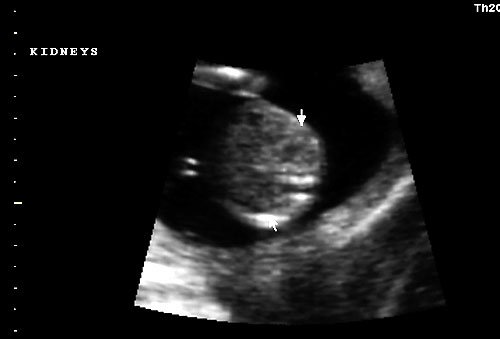

Normal 16 week fetal kidneys |